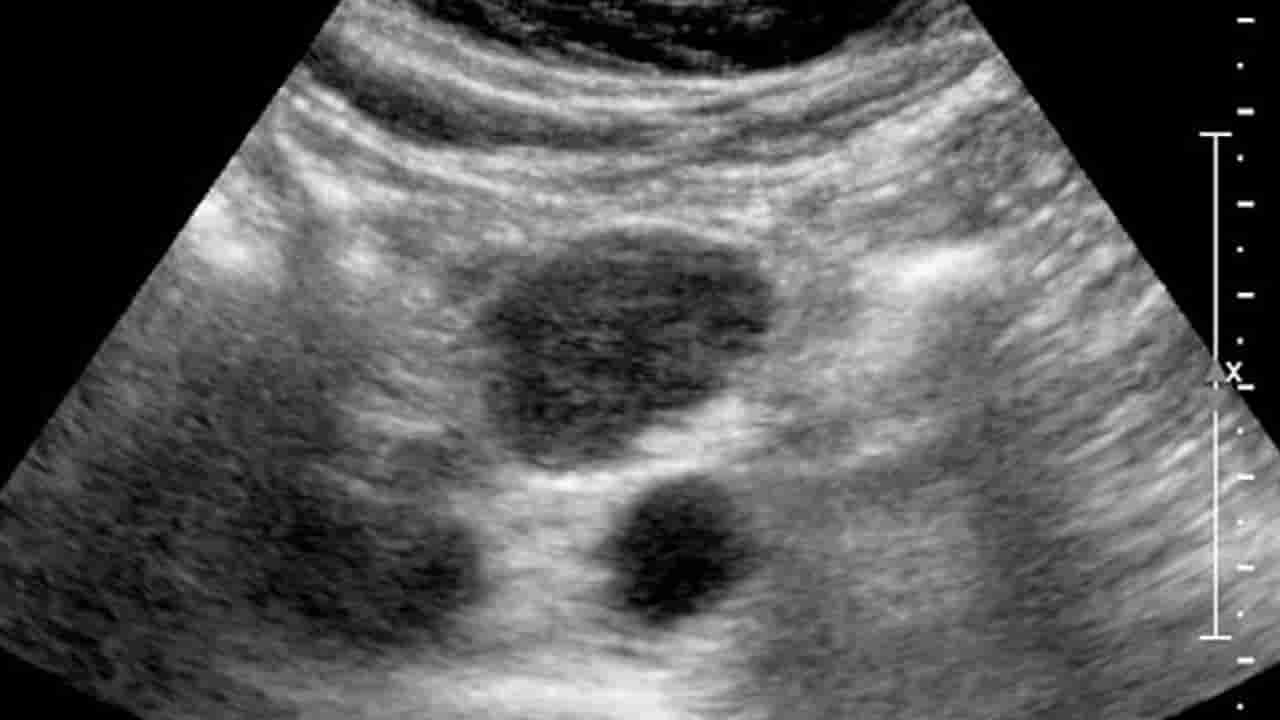

ఇదో విచిత్ర ప్రపంచం. ఎప్పుడు.. ఎక్కడ ఎలాంటి వింత బయటపడుతుందో చెప్పలేం. తాజాగా జార్ఖండ్లో ఓ యువకుడి కడుపులో గర్భాశయం, ఫెలోపియన్ నాళాలు, అండాశయం వంటి స్త్రీ పునరుత్పత్తి అవయవాలను గుర్తించారు వైద్యులు. ఆపరేషన్ చేసి వాటిని తొలగించారు. ఇది అత్యంత అరుదైన ఘటన అని తెలిపారు. ఝూర్ఖండ్లోని గొడ్డా జిల్లాకు చెందిన 22 ఏళ్ల యువకుడికి కడుపులో విపరీతమైన నొప్పి వచ్చింది. దీంతో వెంటనే ఆస్పత్రికి వెళ్లాడు. అక్కడ టెస్టులు చేసిన డాక్టర్లు.. అల్ట్రాసౌండ్ స్కానింగ్ చేసి.. పురుషాంగం వద్ద హెర్నియా ఉన్నట్లు ఐడెంటిఫై చేశారు. రైట్ సైడ్ వృషణం కూడా లేదని నిర్ధారించుకున్నారు.

దీంతో హెర్నియాను రిమూవ్ చేసేందుకు ఆపరేషన్ చేశారు. అయితే శస్త్రచికిత్స చేస్తుండగా వైద్యులు స్టన్ అయ్యారు. యువకుడి కడుపులో అండాశయం, గర్భాశయం, ఫెలోపియన్ నాళాలు ఉన్నట్లు గుర్తించి నిర్ఘాంతపోయారు. ఆపై కుటుంబ సభ్యుల అంగీకారంతో.. ఆపరేషన్ చేసి అతడి శరీరంలోని.. స్త్రీ పునరుత్పత్తి అవయాలను సైతం రిమూవ్ చేశారు.

పెర్సిస్టెంట్ ముల్లెరియన్ డక్ట్ సిండ్రోమ్ కారణంగా పురుషుల్లో.. స్త్రీ పునరుత్పత్తి అవయవాలు అభివృద్ధి చెందుతాయని డాక్టర్లు తెలిపారు. ప్రజంట్ యువకుడి ఆరోగ్య పరిస్థితి నార్మల్ గానే ఉందన్నారు. బాధిత యువకుడి వివరాల విషయంలో గోప్యత పాటించినట్లు తెలిపారు. అయితే ఇప్పటివరకు ప్రపంచ వ్యాప్తంగా దాదాపు 200 మంది పురుషులు ఇలా గర్భశయాన్ని కలిగి ఉన్న కేసులు వెలుగు చూశాయని డాక్టర్లు తెలిపారు.